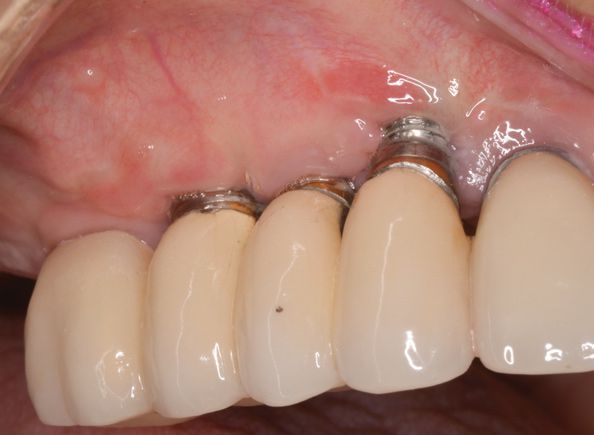

Сопутствующим стоматологическим заболеванием у 6 пациентов (35,29 %) был хронический генерализованный пародонтит в стадии обострения — легкой степени (ХГПЛС), у 11 (64,71 %) — средней степени тяжести (ХГПСС). Контрольную группу составили 5 человек (3 ХГПЛС, 2 ХГПСС), этим пациентам проводилось стандартное лечение (профессиональная гигиена пьезоэлектрическим аппаратом в области имплантатов инструментом с пластиковым покрытием (рис. 3) , удаление налета неабразивными пастами механическим методом.

Многоразовый автоклавируемый инструмент, которым проводилась очистка имплантатов от зубных отложений, имеет полиэфиркетонкетоновое покрытие, безопасное для поверхности имплантатов и керамики, работает с пьезоэлектрическим наконечником посредством присоединения через эндочак на 120 0 (рис. 4) .

Рис. 3. Инструмент PI для профессиональной гигиены имплантатов ультразвуковым методом и его работа в полости рта.

Рис. 4. Инструмент PI для профессиональной гигиены имплантатов ультразвуковым методом и его работа в полости рта.